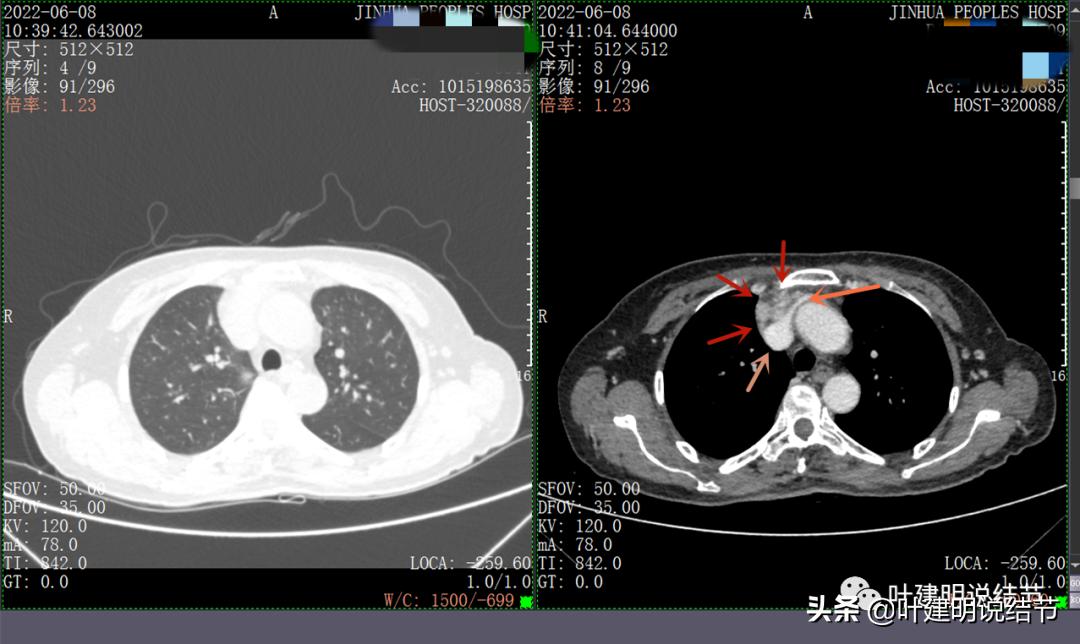

再来看看她的CT增强图像:

以下图片左侧是肺窗,右侧是纵隔窗。红色箭头示病灶,桔色箭头示无名静脉,黄色箭头示支气管,砖色箭头示上腔静脉,蓝色箭头示主动脉,紫色箭头示肺动脉。

病灶胸顶较高位置就出现了,在无名静脉水平

无名静脉略受压